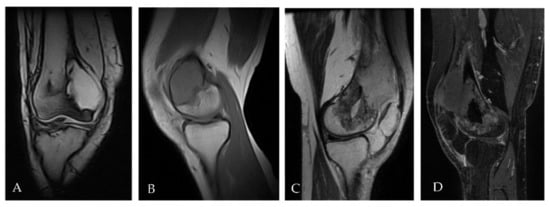

2.1. Patient 1

2.2. Patient 2

2.3. Patient 3

| Age | Sex | ECOG PS | Diagnosis (Date) | Site of Primary GCTB | Surgery | Rec. Date | Treat. Management | Malignant Transformation (Date/Surgery or Biopsy) | Treat. | Evolution | Subsequent CHT Lines | FU/D | Time to MT (Months) | OS from GCTB Diagnosis (Months) | OS from MT (Months) | |

|---|---|---|---|---|---|---|---|---|---|---|---|---|---|---|---|---|

| Pt 1 | 29 | F | 0 | 17 July | Right femur | Curettage and bone grafts | 18 February | Neoadj denosumab (7 cycles) | 18 July Extraarticular resection: high-grade fibroblastic osteosarcoma | ISG/OS-2 | PD | I: IFO II: GEM.TXT III: PAZO | D 22 January | 9 | 53 | 43 |

| Pt 2 | 48 | M | 0 | 16 November | Right tibia | Curettage and bone grafts | 20 October | Neoadj denosumab (6 cycles) | 21 February Extraarticular resection: malignant transformation of GCTB | EURO BOSS | NED | - | FU 21 December | 51 | 64 | 13 |

| Pt 3 | 20 | F | 0 | 10 September | Left femur | Resection of the femoral head, curettage and bone grafts | 11 March | Biopsy | 11 June Biopsy: high-grade osteosarcoma G3 with aberrant expression of beta-HCG | ISG/OS-1 | PD | - | D 11 November | 9 | 14 | 5 |